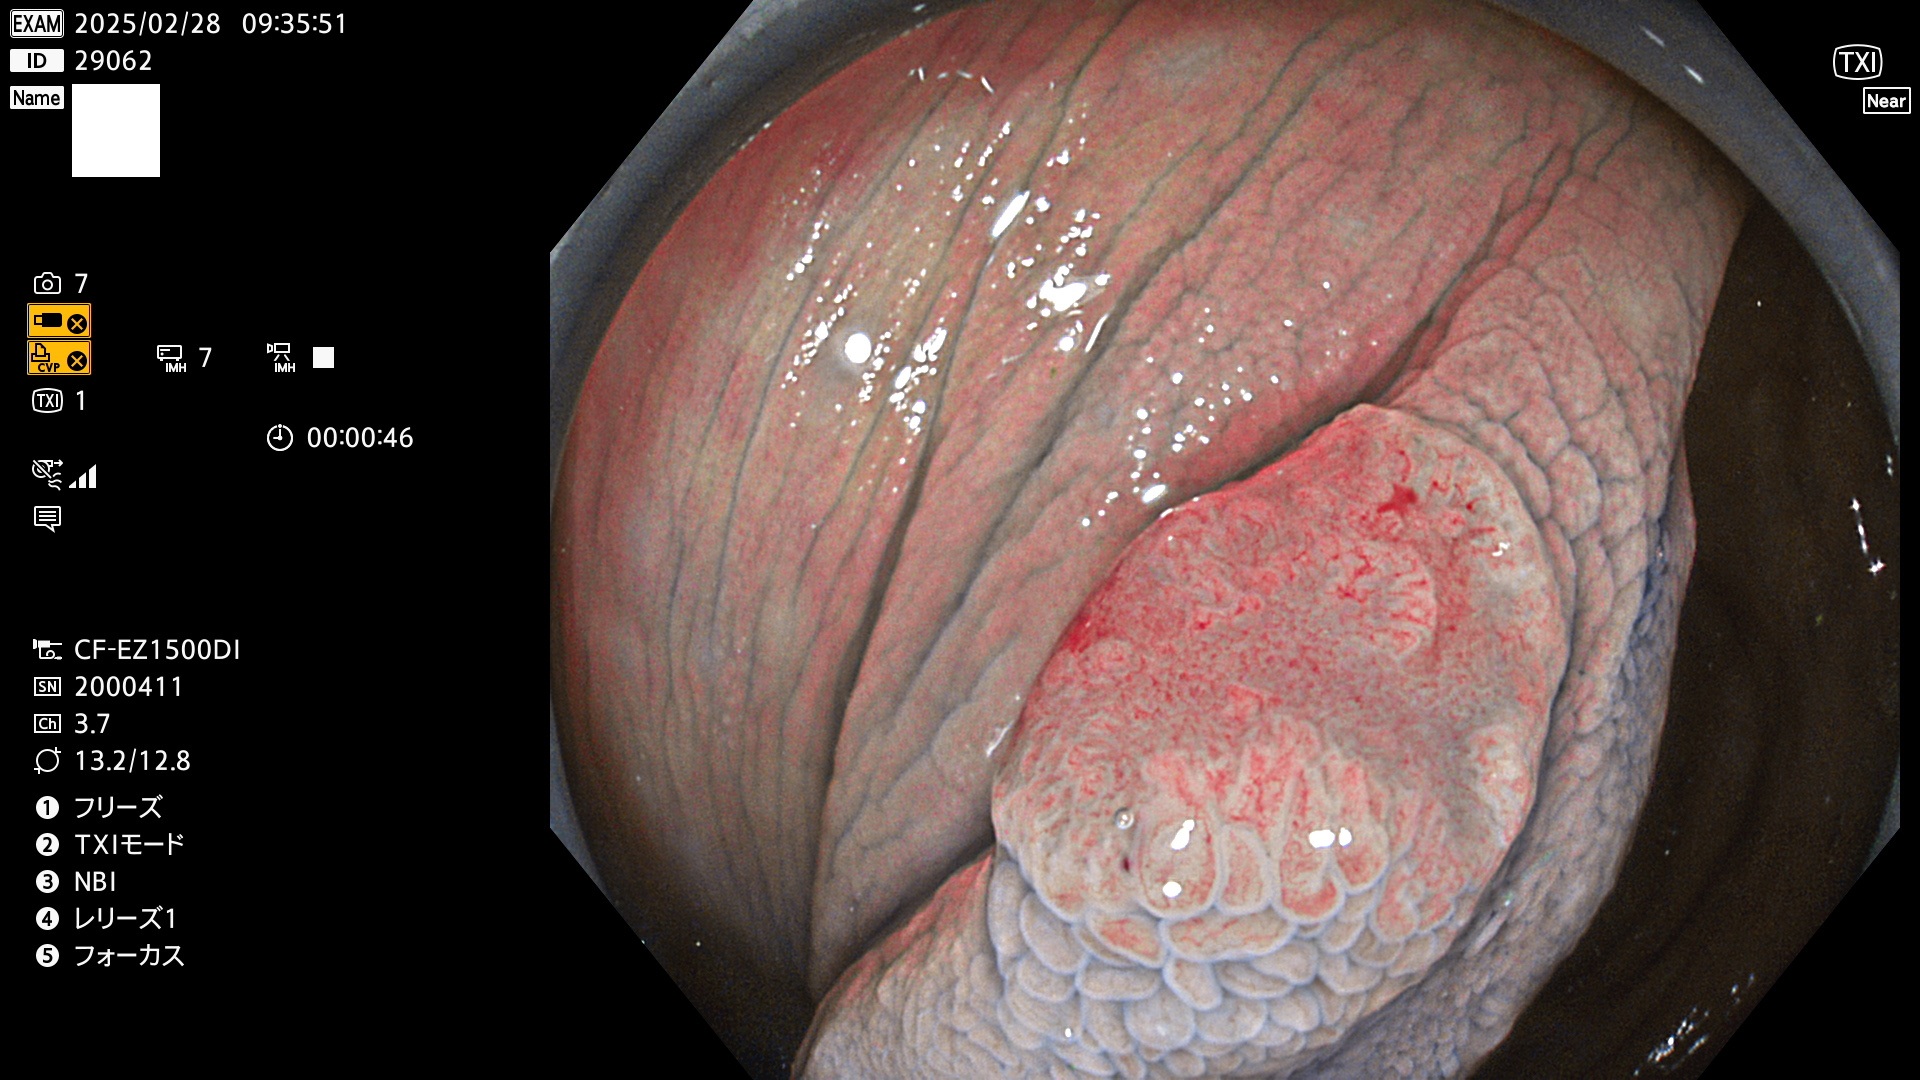

今週のUb、Uc型腺腫

完全に平坦な物をUb、陥凹している物をUcと呼びます。最も発見が難しく危険な病変です。

毎週の検査(木・金・土・日)に発見されたUb、Uc型・腺腫を、その週の日曜の夜にUPし1週間、提示します。

抽出の対象期間 2025年2月27日〜3月2日の4日間(48件の検査)9個 (9/48=19%)